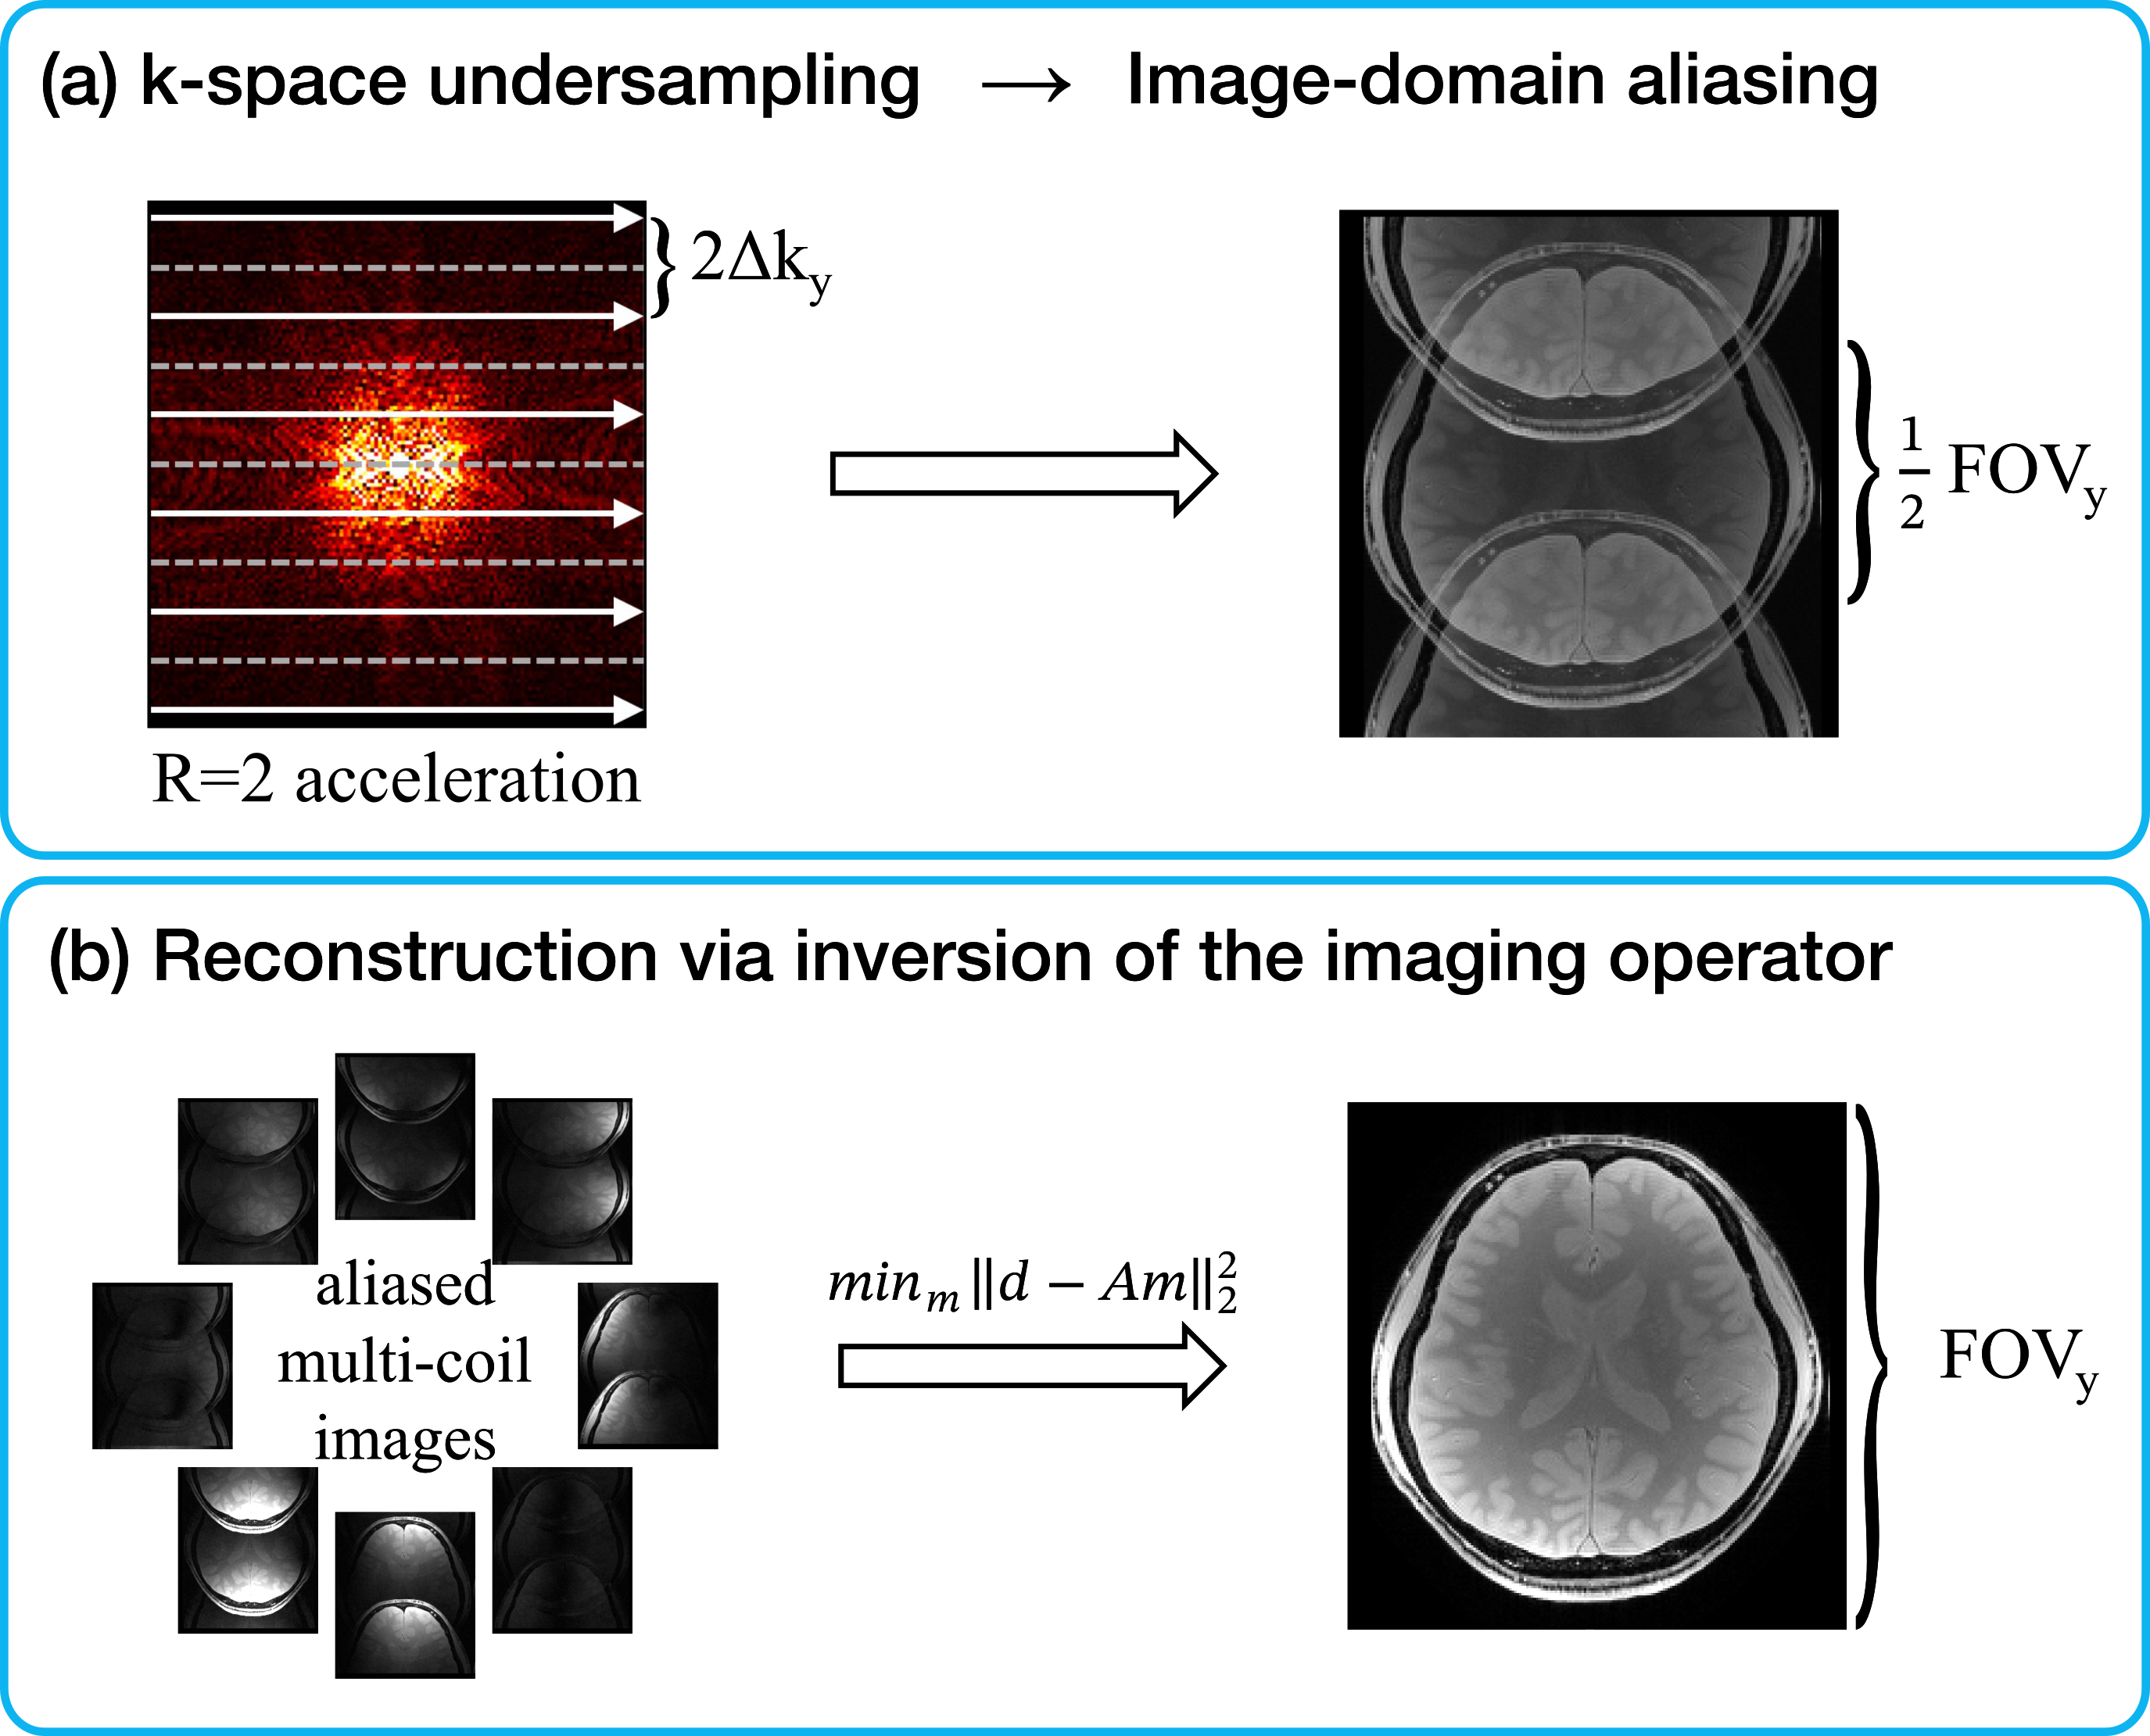

Image reconstruction, i.e., recovering m(𝐫)m(\mathbf{r}) from d(𝐤)d(\mathbf{k}), hence can be cast as an inverse problem aiming to minimize the discrepancy between acquired and reconstructed data, derived via a complex Euclidean norm since noise in MRI data is bivariate Gaussian (Fig. 3):

m=argmin𝑚dAm2,m^{*}=\underset{m}{\mathrm{argmin}}\,||d-Am||^{2}, (13)

Refer to caption

Figure 3: (a) Undersampling in k-space leads to aliasing artifacts in the image domain following inverse Fourier transformation. (b) Multi-coil aliased images are processed to invert the imaging operator AA, which encapsulates the effects of the sampling pattern, Fourier encoding, and coil sensitivities. A reliable inversion can produce an artifact-reduced, coil-combined image that approximates the fully-sampled reference.